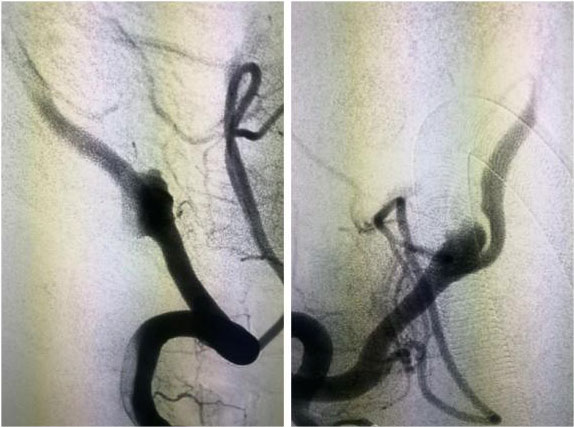

DSA是一种可以清晰观察到血管病变的检查方式。它的全称是数字减影血管造影(Digital Subtraction Angiography, DSA),是将常规血管造影与计算机技术相结合的一种高端诊疗技术。通过穿刺动脉(一般选用右股动脉)放置一动脉鞘和导管,在导丝引导下,从股动脉逆行而上达到主动脉弓,顺行选择所要显示的血管,注入含碘造影剂;同时,将造影剂所经过的血管轨迹连续X光摄片成像。成像后,通过电子计算机去除颅骨和其他软组织的干扰,即可获得清晰的颅内血管显影。

▲ 颅脑侧位DSA显像图

▲ 颅脑正位DSA显像图

DSA不但能清楚地显示颈内动脉、椎基底动脉、颅内大血管及大脑半球的血管图像,还可测定动脉的血流量,所以,目前已被应用于脑血管病检查,特别是对于动脉瘤、动静脉畸形等定性定位诊断,更是较佳的诊断手段。不但能提供病变的确切部位,而且对病变的范围及严重程度,也能清楚地了解,为手术治疗提供可靠的客观依据。另外,对于缺血性脑血管病,也有较高的诊断价值。DSA可清楚地显示动脉管腔狭窄、闭塞、侧支循环建立情况等,对于脑出血、蛛网膜下腔出血,可进一步查明导致出血的病因,如动脉瘤、血管畸形、硬脑膜动静脉瘘等。因此临床上视DSA为诊断脑血管病变的“金标准”。